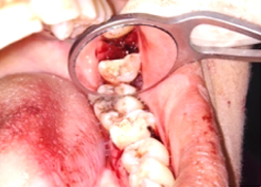

Bone Graft Placement